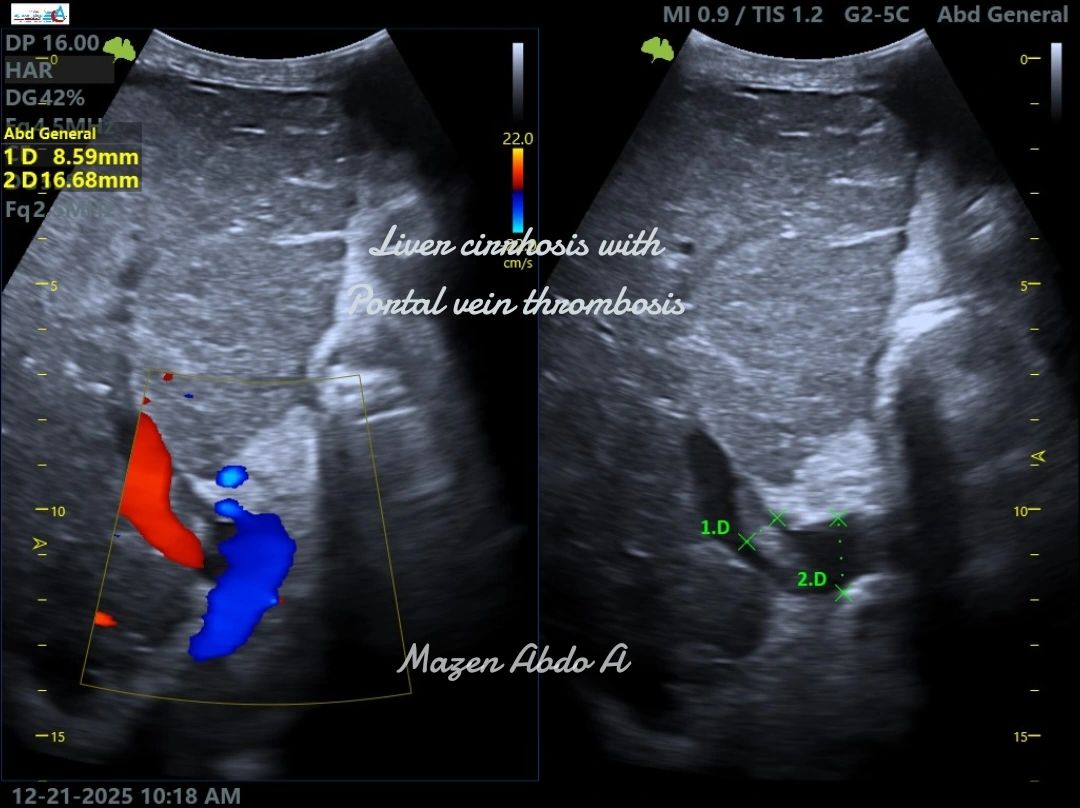

“Ultrasound cases from my daily practice

Liver Cirrhosis with Portal Vein Thrombosis (PVT)

Portal vein thrombosis is a serious complication of liver cirrhosis. On ultrasound, it may appear as echogenic material within the portal vein with absent or reduced Doppler flow. Chronic PVT can lead to portal hypertension, splenomegaly, and the development of collateral vessels. Early detection by Doppler ultrasound is essential for timely management and to reduce complications.”